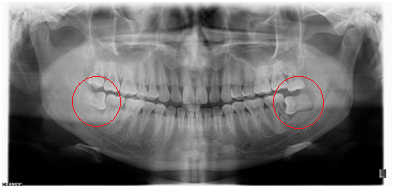

【全景牙片】

◆阻生智齿